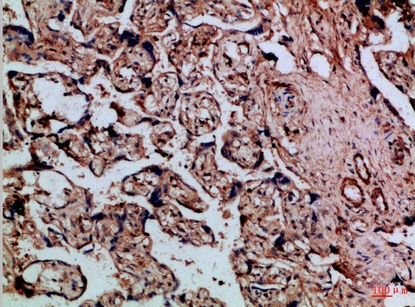

Fig.3. Immunohistochemical analysis of paraffin-embedded Human-placenta, antibody was diluted at 1:100.